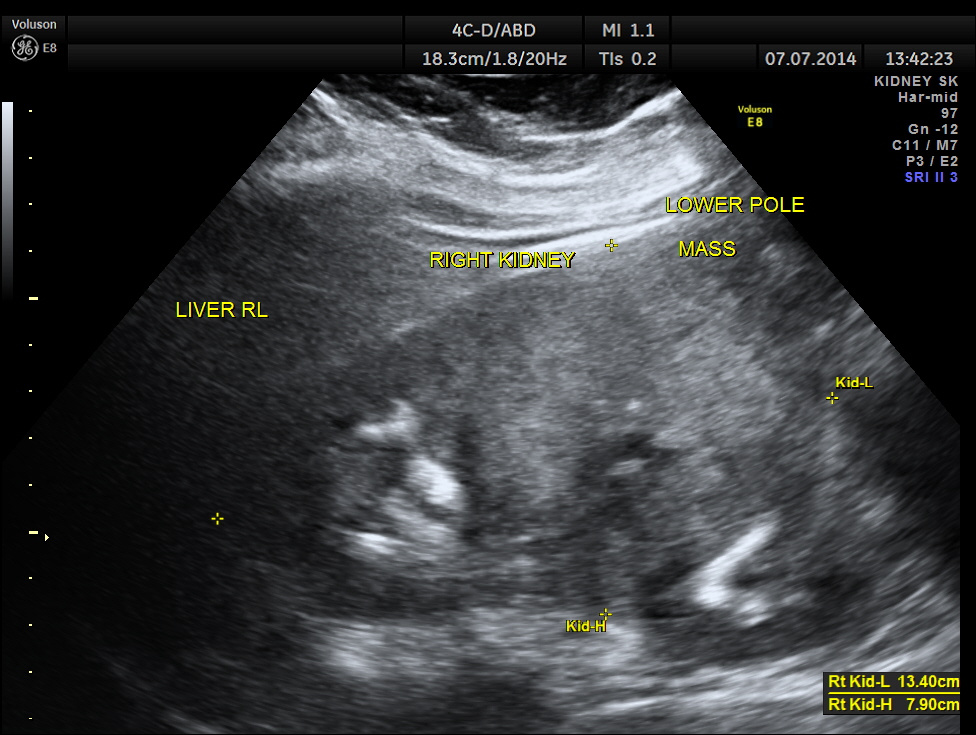

The right kidney is shown below. A solid mass is seen in the lower pole region.

The mass measurements are given below.